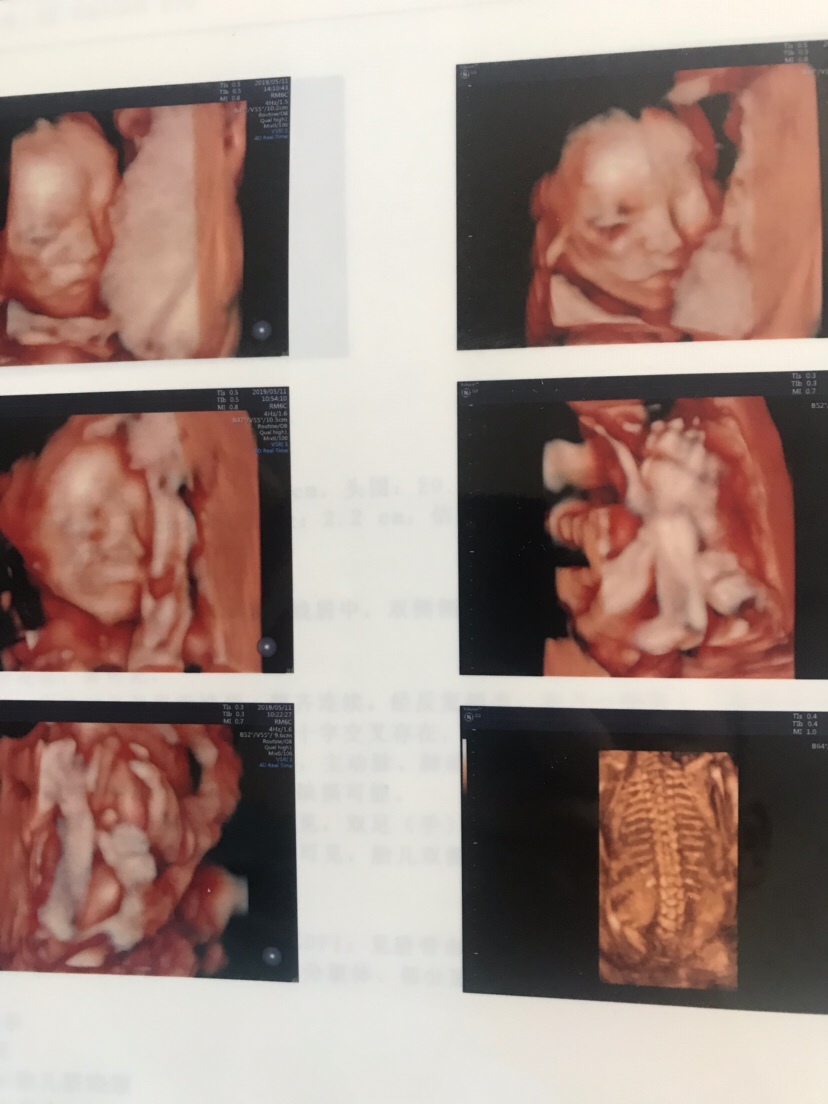

孕 34周+5天